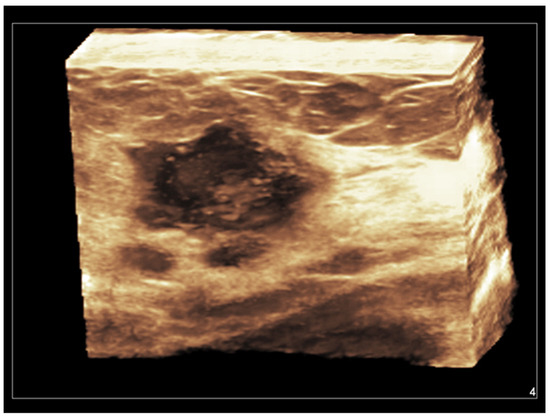

Figure 5. Invasive ductal carcinoma of the breast. Coronal 3D display of infiltrating tumor margins.

2.6. Three-Dimensional Ultrasound

Both hand-held and automated linear transducers are available for use in high-resolution 3D breast imaging. Three-dimensional US, also called volumetric US, allows for obtaining a surface rendering of normal and abnormal breast structures. With a single pass of the ultrasound beam, a 3D reconstructed image is formed in the coronal, sagittal, and transverse planes, allowing a more accurate assessment of anatomical structures and tumor margins [11]. Coronal images, being parallel to the skin, represent a unique opportunity allowed from 3D US. A vivid representation of breast tumors can be obtained, with a retraction, star-like profile strongly supporting the diagnosis of malignancy [70,71,72,73,74] (Figure 5).